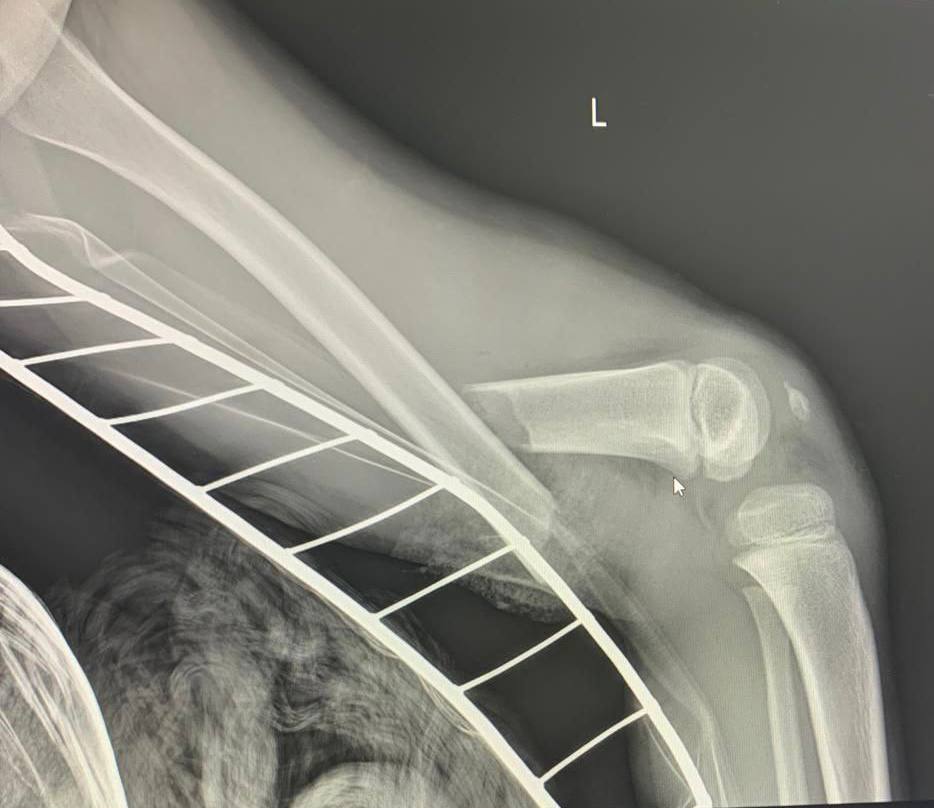

С открытым переломом, разрывом крупных сосудов и большой кровопотерей из поселка Фёдоровский в Сургутскую травматологическую больницу экстренно доставили 6-летнего мальчика. Тяжелую травму ноги он получил, катаясь во дворе на детской карусели.

Пациента принимал дежурный врач травматолог-ортопед Виктор Денисов (фото 3). По его решению в операционную срочно пригласили сосудистых хирургов из Сургутской окружной клинической больницы. Отломок бедренной кости пересёк бедренные вену и артерию. Длительное отсутствие кровоснабжения конечности могло привести к её потере. Нога уже была бледной и холодной. Но благодаря оперативной и высокопрофессиональной медицинской помощи необратимых последствий удалось избежать.

Сегодня ребёнок хорошими темпами восстанавливается в детском отделении травматологии и ортопедии под наблюдением Виктора Денисова, который в течение недели планирует выполнить еще одну операцию – окончательную коррекцию бедренной кости. О выписке из стационара говорить пока рано, но прогноз на перспективу благоприятный: опорная и двигательная функции ноги сохранятся в полном объёме.